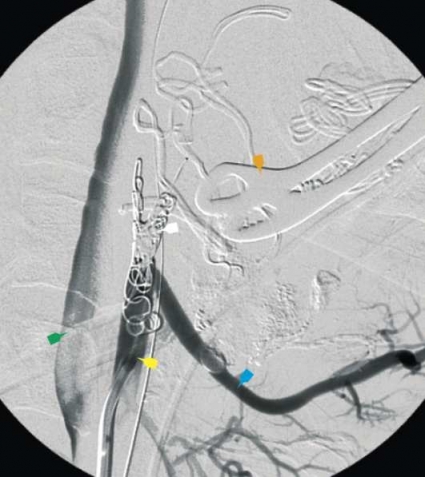

Han överförs direkt till intensivvårdsavdelningen, och inlagda kompressionstorkar fastsatta på peanger avlägsnas försiktigt. I det läget föreligger en mindre, sivande blödning basalt i vänster tonsillbädd. Det blödande området diatermeras. Eftersom det kliniska förloppet talar för en större kärlskada utförs direkt en karotisangiografi med planerad selektiv embolisering av blödningskällan. I samband med kateteriseringen av vänster arteria carotis externa börjar patienten plötsligt att blöda profust från vänster tonsillbädd. Kärlskadan lokaliseras angiografiskt till avgången för arteria facialis från arteria carotis externa (Figur 1–3). Ett första försök att stoppa blödningen selektivt i arteria facialis med intraarteriellt vävnadsklister misslyckas. Genom kraftig intern och extern kompression mot halsen kan blödningen hållas någorlunda under kontroll. I detta dramatiska läge beslutas att ockludera arteria carotis externa. Kärlet emboliseras med användande av platinacoils (Figur 4). Blödningen avstannar då omedelbart.

Patienten får, förutom de tidigare givna nio enheterna blod, ytterligare två enheter blod under emboliseringens gång. När blödningen avstannat ligger Hb på 85 g/l. Han extuberas den 18 januari, ett dygn efter tonsillektomin. Hb har då stigit till 105 g/l utan ytterligare transfusion. Patienten får efter väckningen feber och andningsbesvär och har en förhöjd puls på 120 slag/minut. Röntgen visar en atelektas av ovanloben på höger lunga. En snabb förbättring inträder efter antibiotikabyte, syrgastillförsel och fysikalisk behandling.